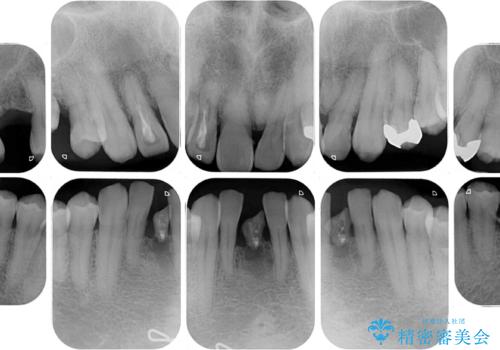

- むし歯治療途中で放置された歯が多く、スペースができたり歯が寄って来たりしているのを気にして来院された患者様です。

矯正治療を行いながら、欠損部はインプラントによる補綴治療を希望されたため、補助装置を用いたワイヤー矯正によりスペースを確保しながら歯列を整え、適宜インプラントを埋入していくこととしました。

上顎前歯もインプラントを希望していらっしゃいましたが、両隣の歯根が近接しており、インプラントは困難と判断したためオールセラミックブリッジによる補綴治療を前提として治療を開始することとしました。